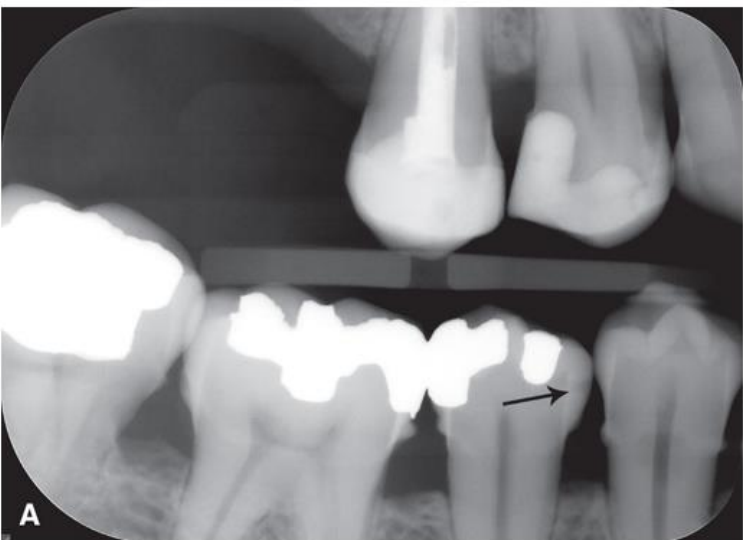

top arrow, classify this lesion based on the ADA caries classification system

D1

bottom arrow, classify this lesion based on the ADA caries classification system

D2